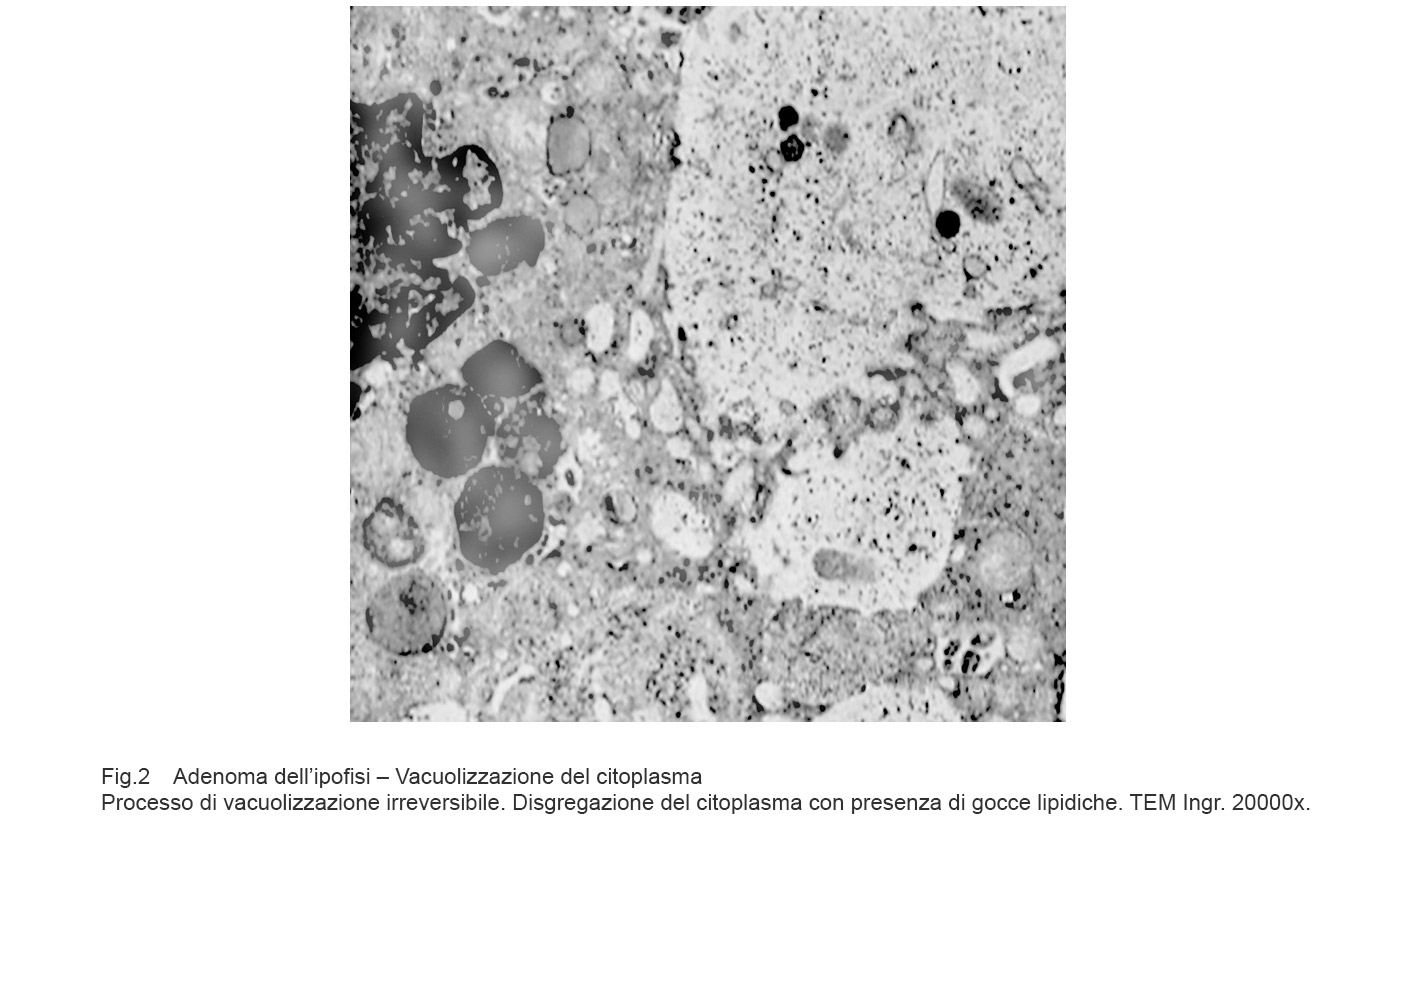

Nel processo di necrosi, la cellula aumenta di volume, si rigonfia per il blocco delle pompe ioniche e conseguente penetrazione nel citosol di acqua e sodio.

Si ha il quadro di un processo vacuolare irreversibile pre-necrotico con disaggregazione dello assetto degli organuli intracitoplasmatici, grave rigonfiamento dei mitocondri, dilatazione abnorme delle cisterne del retico endoplasmatico, perdita dei ribosomi, disgregazione del nucleo per rottura della membrana nucleare.

Fig.2